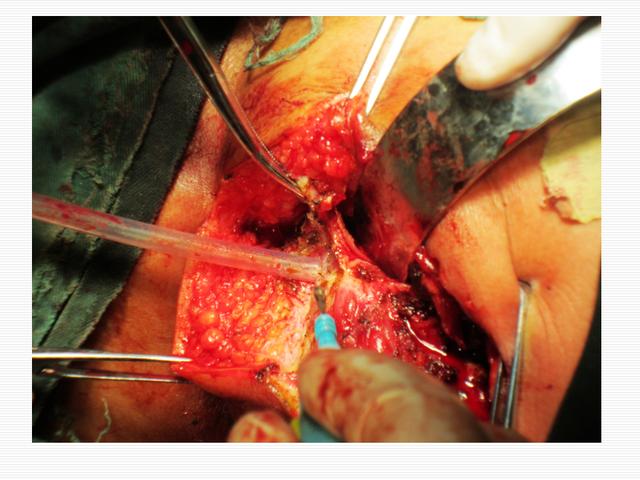

手术案例:高位肌间马蹄形肛瘘行tropis 肛管后间隙切开一例

马蹄形肛瘘手术图片